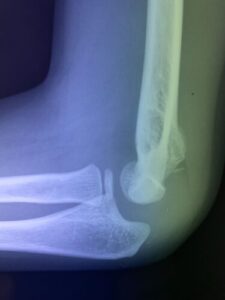

第24回整骨研究会「賜恩」研修会開催

春日部市市民活動センター(肘関節脱臼)

肘関節前方脱臼の1症例について